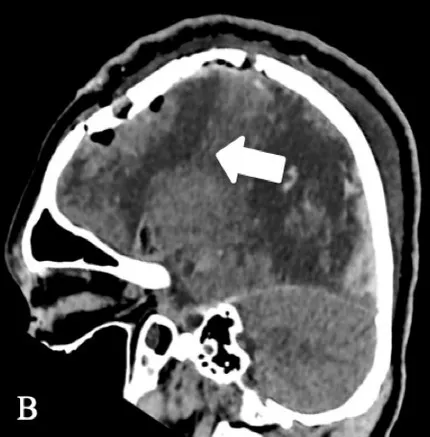

| Patient 1 | Pathology: Residual left-hemispheric pathology. |

|

| M, 12 years | Seizures: Daily asymmetric tonic spasms provoked by unexpected tactile and auditory stimuli. | ||

| Neurological examination: Mild right-sided hemiparesis. | |||

| MRI: Axial T2 with a small cortical remnant on the left parasagittal (white arrow in Figure A). | |||

| Wada test: Confirmed right leg motor functionality of the parasaggital cortical remnant. | |||

| Surgery: Modified hemispherotomy after intra-operative monitoring (IONM) and preservation of the right leg motor function (early sagittal CT showing the descending fibers from that area, white arrow on Figure B). | |||

| Follow-up: Early postoperative seizures for 1 week, then >1 year seizure-free. | |||